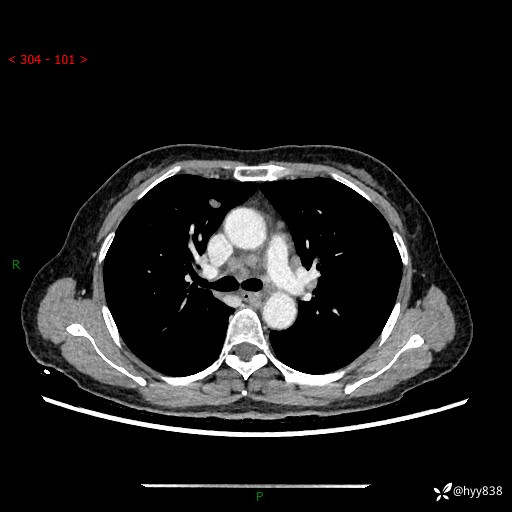

【患者信息】:58岁/女

【主诉】:体检发现肺结节

【检查】:胸部CT平扫+增强

结节病 (44)

小细胞癌 (19)